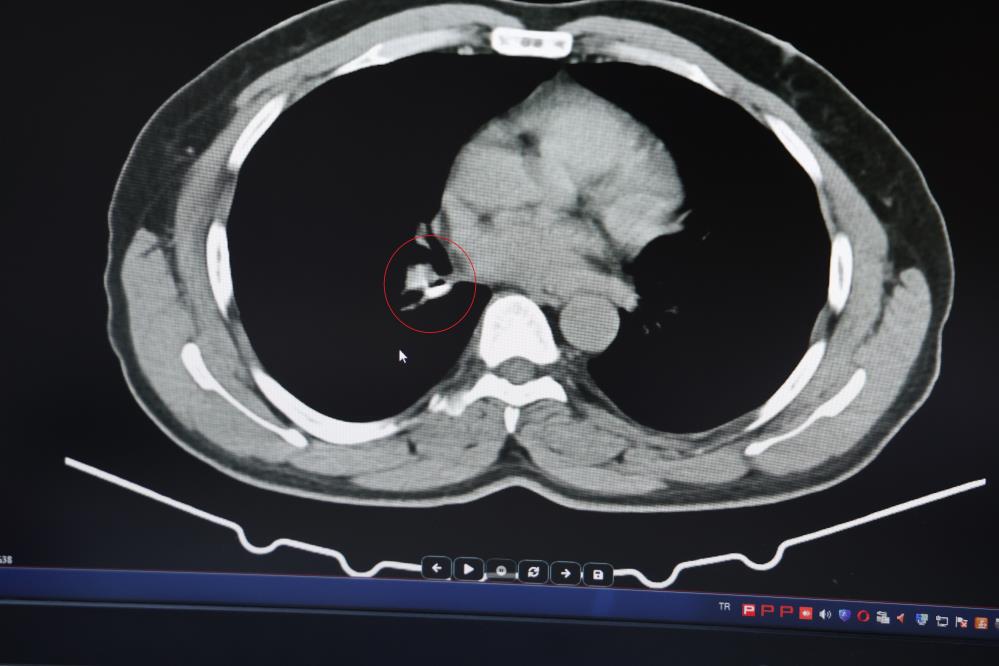

Şenyiğit, o maddenin zamanla akciğer yapısının özelliğini aldığını ve orada yabancı bir madde olarak kaldığına değinerek, "Hastamıza maalesef 2 yıldan beri astım tanısı konulmuş ve sürekli tedavi verilmiştir. Hasta bize geldiği zaman yapılan tomografide sağ akciğer ana bronşun distalinde şüpheli lezyon gördük. Uyguladığımız bronskokopide yabancı maddenin silikon olduğunu tespit ettik. Onu çıkardıktan sonra da hastada bir rahatlama meydana geldi" dedi.